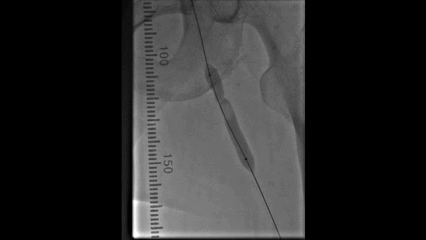

球囊扩张

使用4×150mm球囊扩张髂静脉段和股深静脉段

10mm球囊扩张左侧股深静脉、髂外静脉和髂总静脉

扩张后髂股静脉仍处于闭塞状态,有弹性回缩

支架置入

从股深静脉相对健康管腔开始

从远心端向近心端依次植入12mm支架1枚,14mm支架3枚

所有支架均为自膨式支架,近心端到达下腔静脉水平

10mm球囊对支架进行后扩